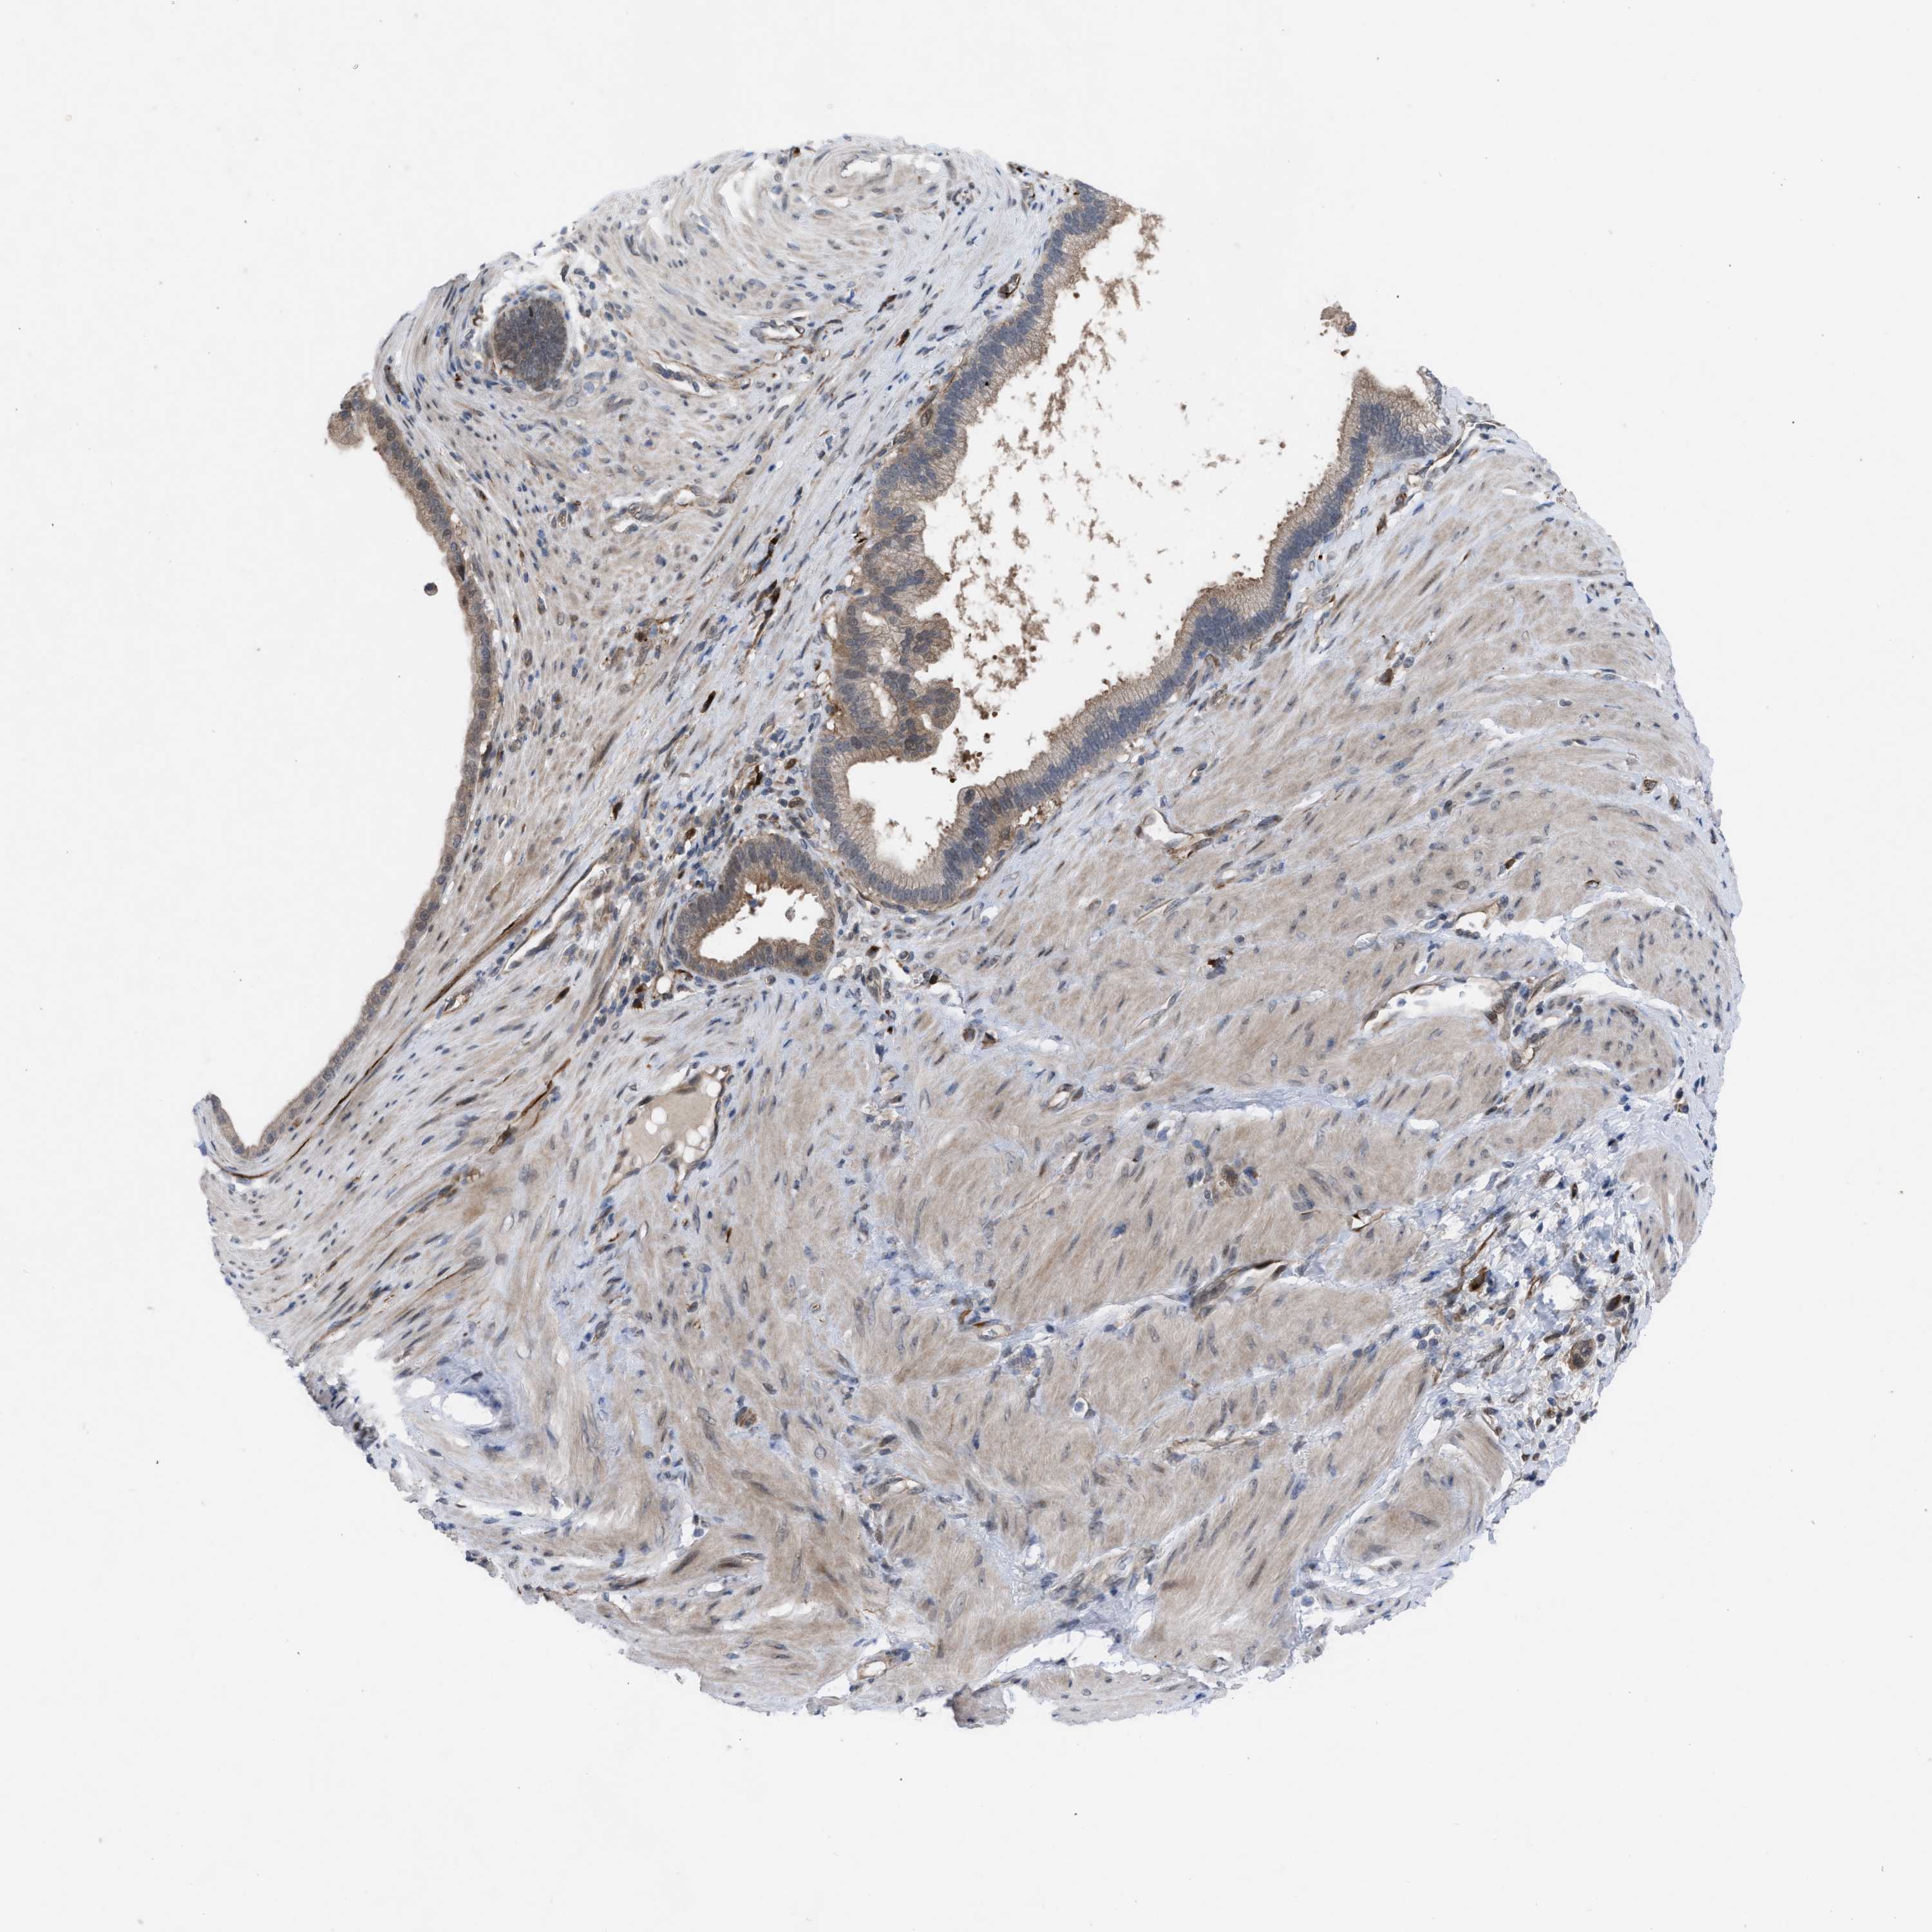

PANCREATIC CANCER - Protein expressioni

A mouse-over function shows sample information and annotation data. Click on an image to view it in a full screen mode. Samples can be filtered based on level of antibody staining by selecting one or several of the following categories: high, medium, low and not detected. The assay and annotation is described here.

Note that samples used for immunohistochemistry by the Human Protein Atlas do not correspond to samples in the TCGA dataset.

Antibody stainingi

Antibody staining in the annotated cell types in the current human tissue is reported as not detected, low, medium, or high, based on conventional immunohistochemistry profiling in selected tissues. This score is based on the combination of the staining intensity and fraction of stained cells.

Each image is clickable and will lead to virtual microscopy that enables deeper exploration of all samples and also displays staining intensity scores, fraction scores and subcellular localization as well as patient and tissue information for each sample.

Antibody HPA019011

Staining

High

Medium

Low

Not detected

Intensity

Strong

Moderate

Weak

Negative

Quantity

>75%

75%-25%

<25%

None

Location

Nuclear

Cytoplasmic/membranous

Cytoplasmic/membranous,nuclear

Adenocarcinoma, NOS